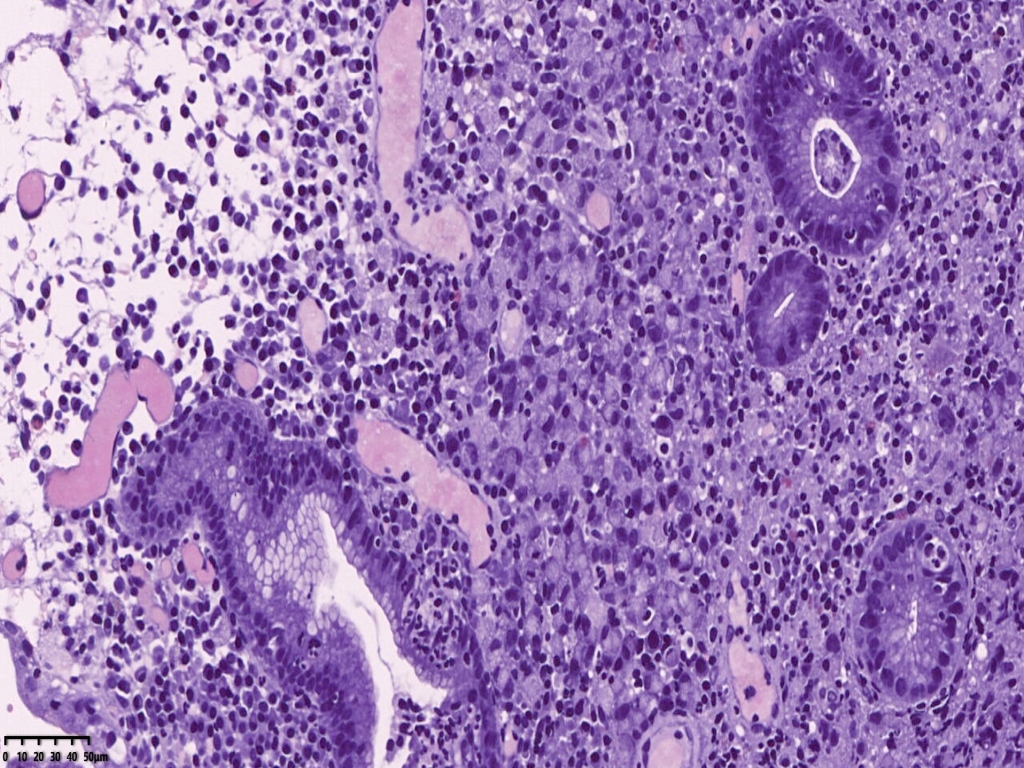

镜下可见胃活检组织,炎症背景明显,小凹及固有腺体结构大致正常,但是其中一块组织内固有层内可见小片状弥漫分布的上皮样异型细胞,组织细胞?浆细胞?溃疡直径大于1厘米,应首先除外肿瘤。

免疫组化常规片内异型上皮细胞更显著。核偏位的异型上皮细胞,胞浆似泡沫样,但是与组织细胞不同,组织细胞核位于中央,与印戒细胞也不太一样,印戒细胞胞浆内为明显的粘液空泡。